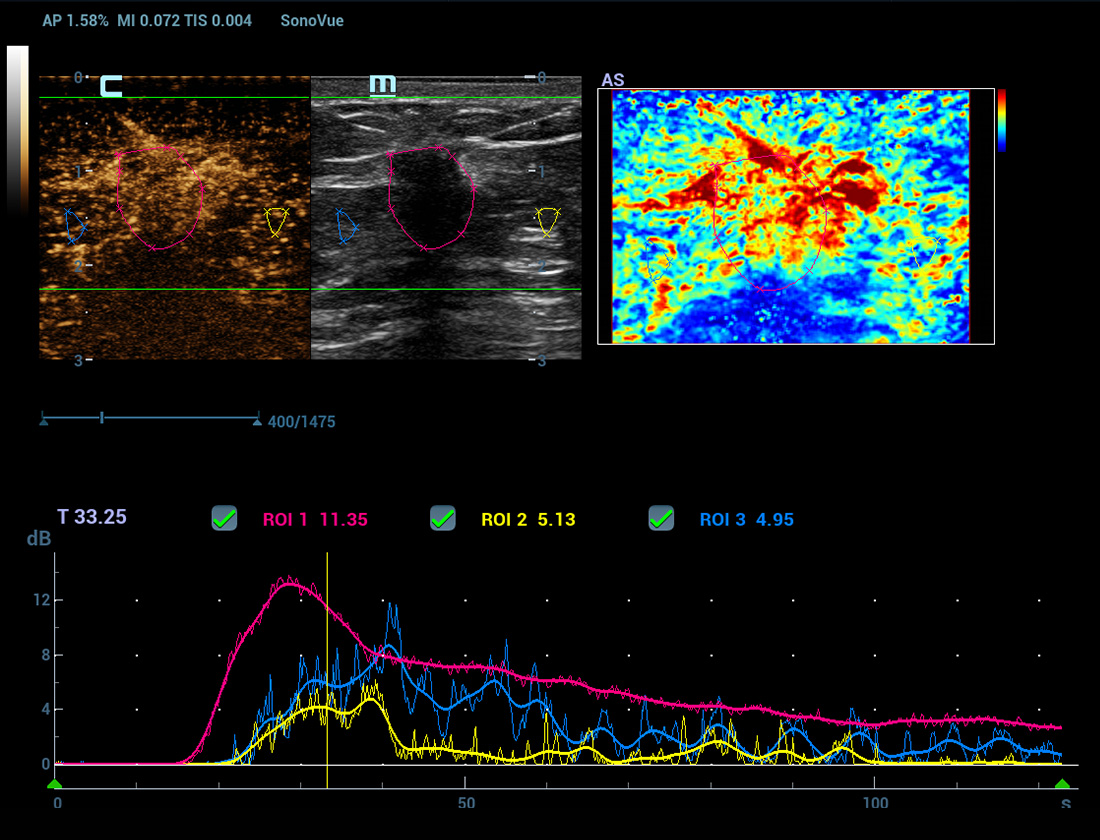

M-Ref. C&E

M-Ref. C&E ã Tumor maligno de mama

M-Ref. C&E permitea exibi??o do contraste e da STE em um û¤nico plano para avalia??o comparativa de perfus?o e elasticidade.

Nova anûÀlise de quantifica??o do CEUS

CEUS QA ã Tumor maligno de mama

A curva tempo-intensidade permite a anûÀlise quantitativa das imagens de CEUS. A nova QA CEUS fornece ferramentas de anûÀlise quantitativa de ponta para ajudar na avalia??o de tumores e na pesquisa clûÙnica.